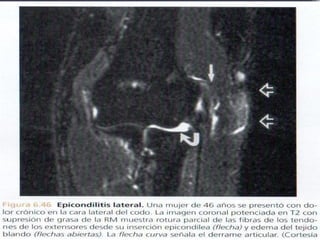

Lesiones de lostejidos blandos • Epicondilitis lateral • Tensión repetida sobre los (codo de tenista) músculos y tendones adyacentes a la cara lateral del ▫ 35 a 55 años húmero distal. ▫ Dolor gradual • Tendón extensor corto radial agravado por la del carpo actividad en la cara • Avascularidad y calcificación lateral de la del tendón articulación del codo. • Epicóndilo lateral. ▫ Tennis, golf y carpinteros

• Epicondilitis lateral    • Tensión repetida sobre los

(codo de tenista)            músculos y tendones

adyacentes a la cara lateral del

▫ 35 a 55 años               húmero distal.

▫ Dolor gradual            • Tendón extensor corto radial

agravado por la            del carpo

actividad en la cara     • Avascularidad y calcificación

lateral de la              del tendón

articulación del codo.   • Epicóndilo lateral.

▫ Tennis, golf y

carpinteros